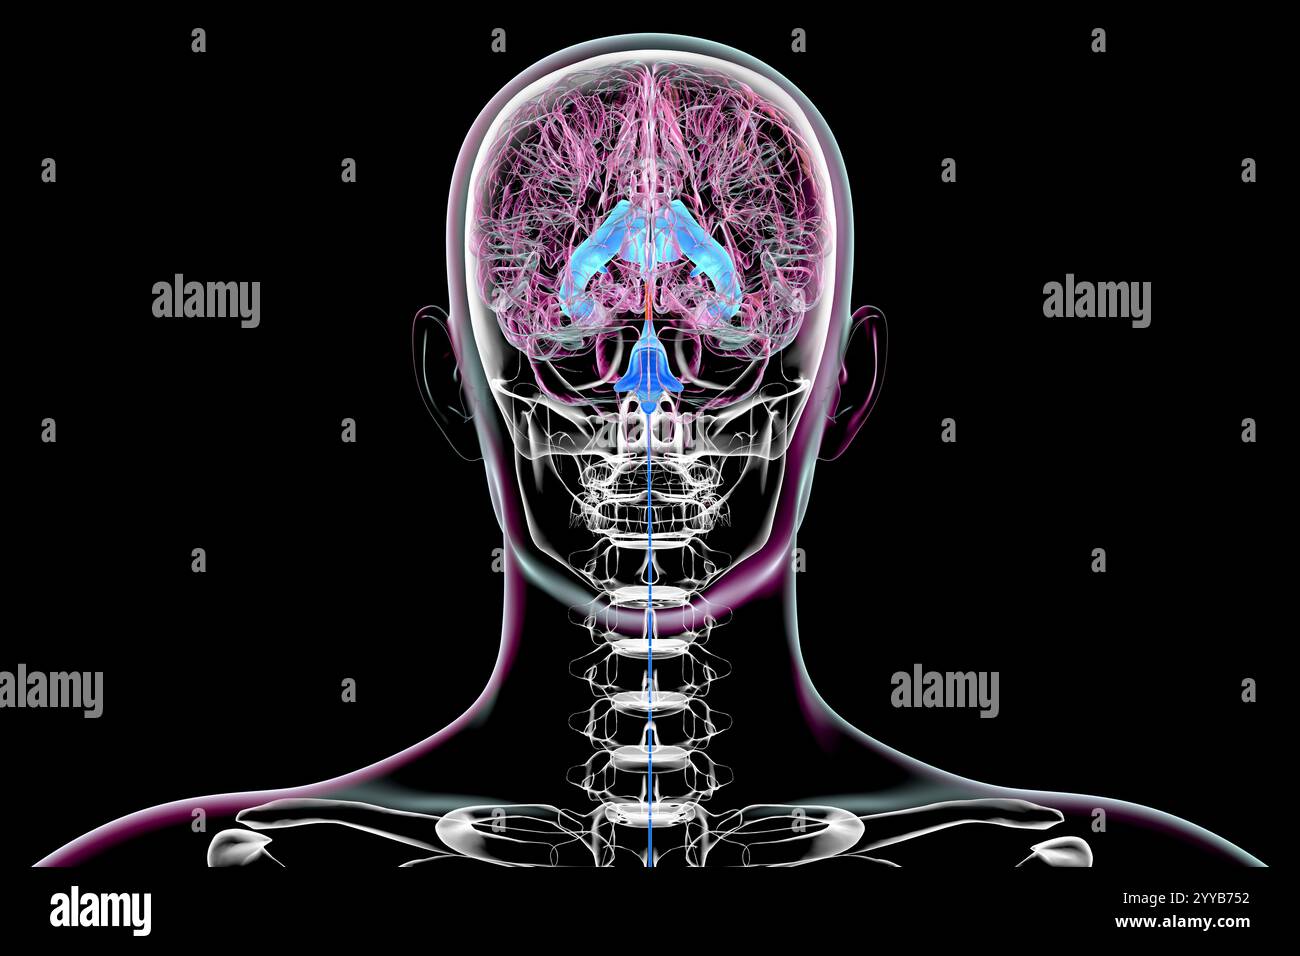

RF2T7NGWH–Ventrikel und zerebrales Aquädukt laterale Röntgenansicht 3D-Rendering-Illustration. Menschliches Gehirn und Ventrikelsystem Anatomie, Medizin, Gesundheitswesen, Scienc

RF2T7NGWK–Ventrikel und zerebraler Aquädukt lateral in Farben Röntgenbild-3D-Rendering-Illustration. Menschliches Gehirn und Ventrikelsystem Anatomie, medizinisch, gesund

RF2T7NGWR–Ventrikel und Hirn-Aquädukt-Röntgenprofil Nahansicht 3D-Rendering-Illustration mit Körperkonturen. Anatomie des menschlichen Gehirns und des Ventrikelsystems,

RF2T7NGWW–Ventrikel und zerebraler Aquädukt in Farben Röntgenprofil Nahansicht 3D-Rendering-Illustration. Anatomie des menschlichen Gehirns und des Ventrikelsystems, medizinisch,

RF2T030FH–Röntgenprofilansicht des Sylvius oder des zentralen Aquädukts des Gehirns 3D-Rendering-Illustration. Menschliche Körperanatomie, Medizin, Biologie, Wissenschaft, Neurowissenschaft,

RF2T6AR8J–3D-Rendering-Illustration für die Röntgenansicht des Gehirns oder des Sylvius aquädukt. Anatomie des menschlichen Gehirns und des Ventrikelsystems, Medizin, Gesundheitswesen, Biologie, Wissenschaft,

RF3C7H8A8–Abbildung des Gehirns mit hervorgehobenem Aquädukt (rot) und ventrikulärem System (blau), Darstellung des Liquorflusses.

RF3C7H8A6–Abbildung des Gehirns mit hervorgehobenem Aquädukt (rot) und ventrikulärem System (blau), Darstellung des Liquorflusses.

RF3C7H8AA–Abbildung des Gehirns mit hervorgehobenem Aquädukt (rot) und ventrikulärem System (blau), Darstellung des Liquorflusses.

RF3C7H8AF–Abbildung des Gehirns mit hervorgehobenem Aquädukt (rot) und ventrikulärem System (blau), Darstellung des Liquorflusses.

RF3C7H8A3–Abbildung des Gehirns mit hervorgehobenem Aquädukt (rot) und ventrikulärem System (blau), Darstellung des Liquorflusses.